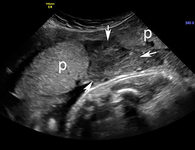

Descolamento da placenta

Imagem de ultrassonografia de descolamento da placenta: a placenta normal está marcada com 'p'; área de descolamento indicada por setas brancas

Do acervo de Dr Y Oyelese; usado com permissão